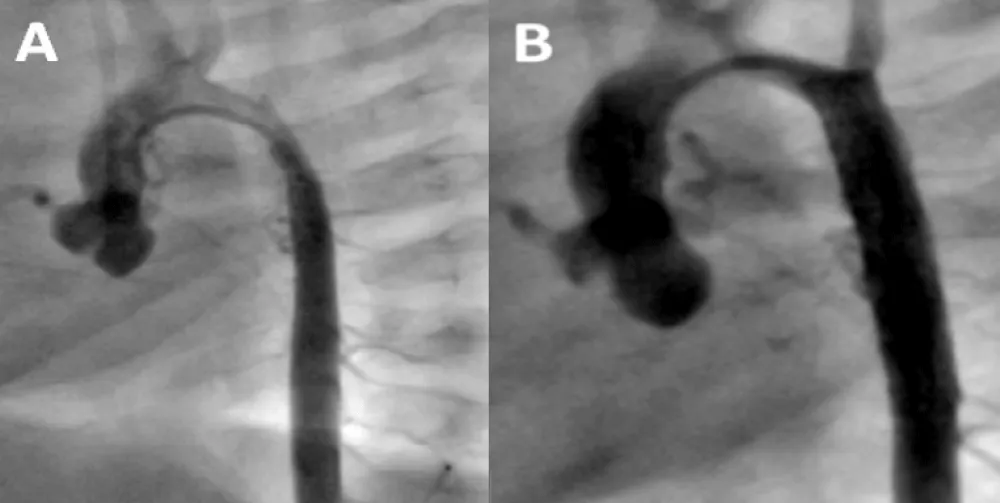

A 5 month-old male, 5 kg weight, with WS phenotype confirmed by FISH test, had an end-to-end anastomosis for severe COA at age one week. He was referred for irritability and poor weight gain. Femoral pulses were absent with upper limb systolic blood pressure of 190 mmHg. A multi-slice CT showed left aortic arch with bi-carotid trunk and recurrent coarctation measuring 1.9 mm in diameter while the transverse arch, the mid aorta, and the aorta at diaphragm level measured 2.8, 3.6, and 5.0 mm respectively (Figure 1). Associated anomalies were moderate right PAS, inguinal hernias, and horseshoe kidney.

Figure 1: Multi-slice CT at the age of 5 months. There is recurrent coarctation of the aorta (arrow) with hypoplasia of the transverse arch extending to the thoracic aorta (see text for diameters at different levels).